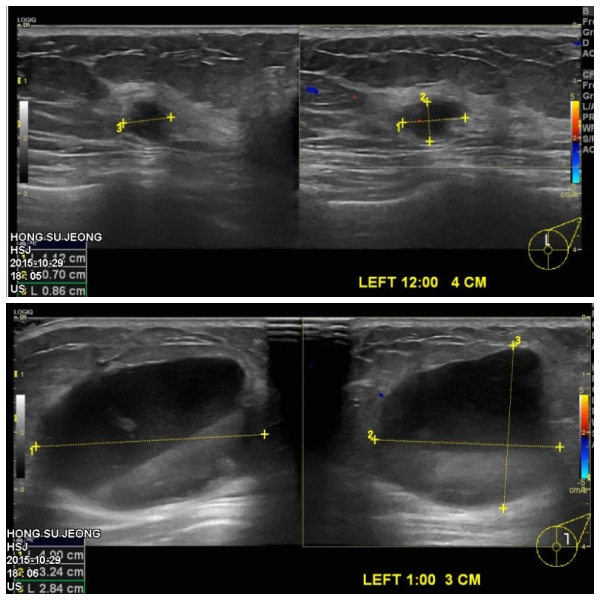

좌측유방에 만져지는 멍우리로 내원하신 60대 환자분이십니다.

본원에서 유방초음파후 좌측유방에 12시방향과 1시방향에 의심되는혹 조직검사 시행하였고

두군데 모두 침윤성 유관암 진단되었습니다.